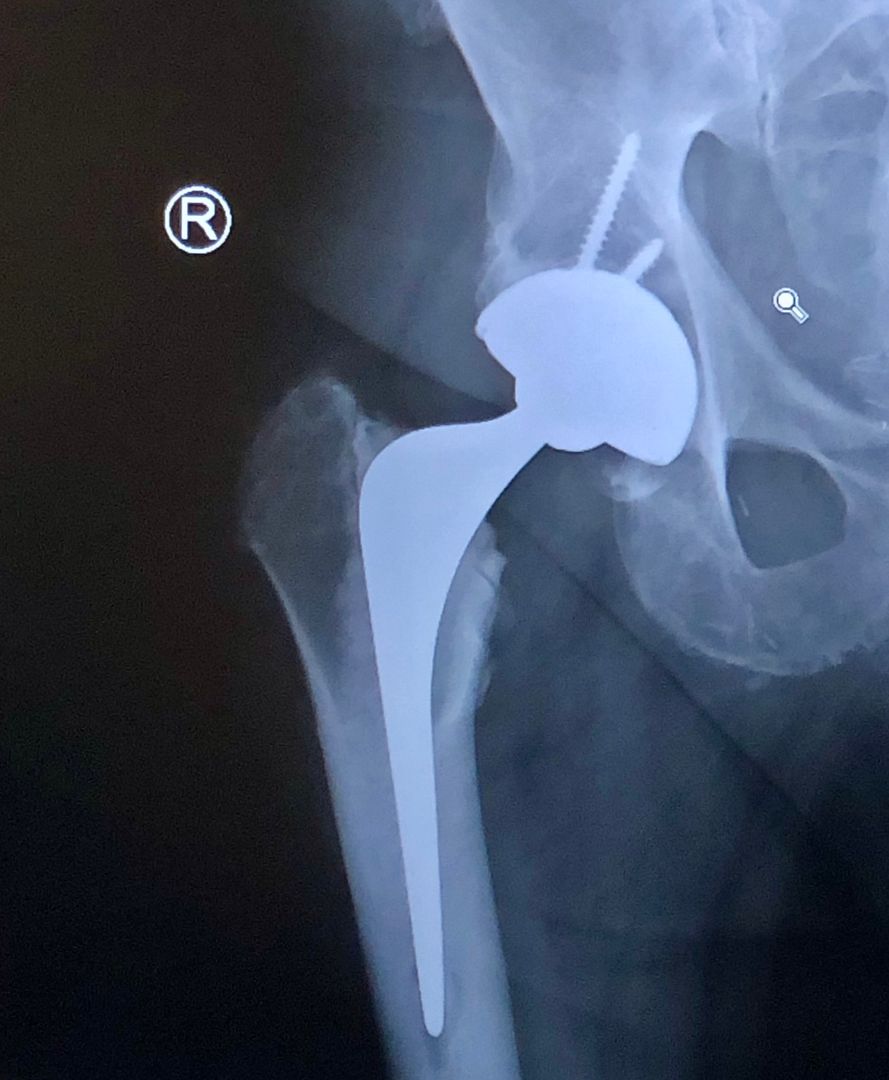

Had one done in October. Minimally invasive rather than the old long scar with staples. Basically parted the misch longitudinally and the whole thing left me with a three inch scar. No stitches. They just glued it closed.

Had one done in October. Minimally invasive rather than the old long scar with staples. Basically parted the muscle longitudinally and the whole thing left me with a three inch scar. No stitches. They just glued it closed.

I had a metal resurfacing in July, now I'm going like a clipped cat.

OP, is it a metal resurfacing your wife's considering? I was under the impression that women getting them is frowned upon in the UK? If she can indeed have it then it's defo the way to go. THR materials are much better these days and so last a lot longer but resurfacing takes away a lot less bone leaving a lot more to play with if a second op becomes necessary at some point, which it prob won't with a resurfacing anyway.

I do have a long scar to show for it, and there was a horrendous amount of swelling for a fortnight after the op but it all settled down quite quickly. Having watched the op on Youtube I can see why there was so much swelling, they don't mess about. Also because with metal resurfacing they don't take much bone away they have a lot less room to work which is why they are prob rougher than with a THR, leading to more swelling. As I understand it metal resurfacing is more "painful" initially post-op but recovery after that initial period is much better than with THR. Here I am at 5 months absolutely desperate to go skiing to test it out. My hip feels great and I have a new lease of life. Just need my knee replaced now grrrrrr. All of the above is my opinion of course, your wife needs proper surgical advice.

You would be best getting this information from a hip surgeon. Its very complicated and very patient specific. I don't do hips.Resurfacing can be a good option, but it isn't the panacea that it was touted to be 10 years ago. There is also a problem with metal on metal bearings in some Total Hip Replacements (THR)

Absolute proportions of resurfacing vs THR in the UK is down at <1%. In fact it looks like only 66 NEW resurfacings were done in the UK in 2019 See the 17th annual NJR report https://reports.njrcentre.org.uk/ Page 45/46. - 312 page report on joint replacement that is produced every year.

Hip replacements are very successful procedures. Something like 98%+ of patients can’t feel or tell they have a replacement hip in terms of pain or mobility, it’s a life changing operation.

Life of a THR is 10 to 20+ years depending on activity level and how well it is fitted. I think aseptic loosening is now the most common failure mode, but tends to take a long time. Revisions are costly and generally have a much shorter life than the original and a second or third revision is sometimes not possible.